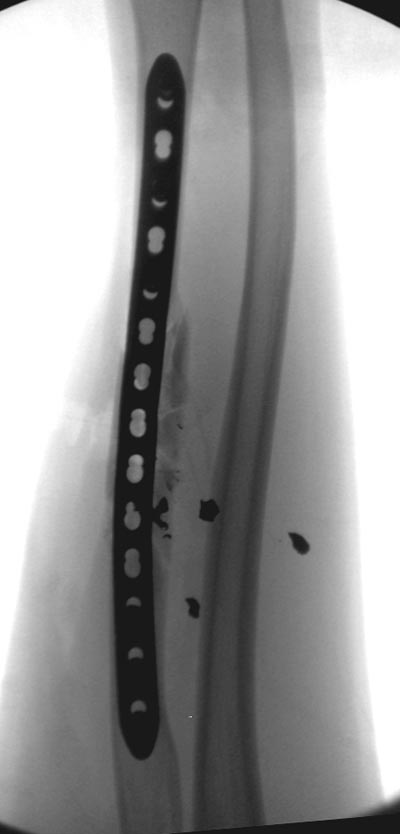

Здесь примеры: двоюродные братья с ранением предплечья, у одного

локтевая, а у второго лучевая. В следующее утро локтевая фиксирована без

обнажения фокуса травмы из небольших доступов, а второй из обычного

волярного доступа. А клинический снимок из прошлых операций...